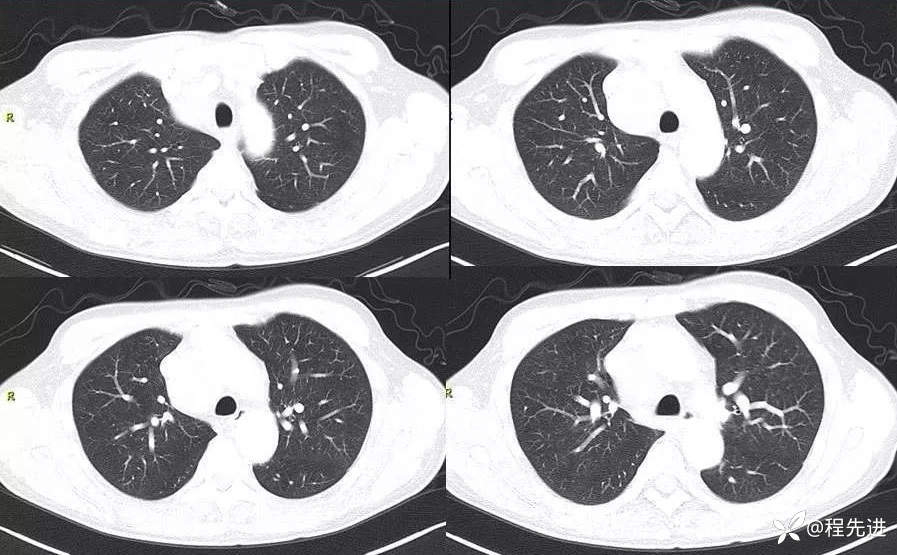

肺窗